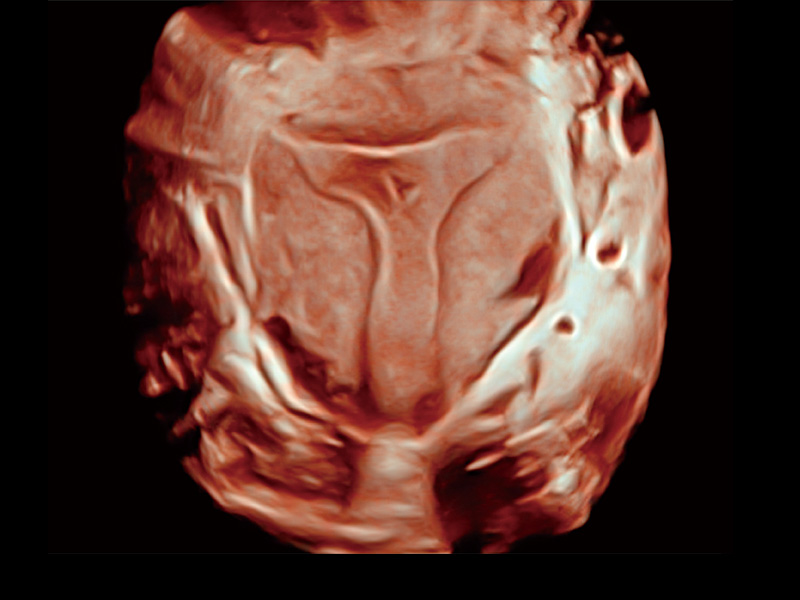

临床图

卵巢多囊样改变